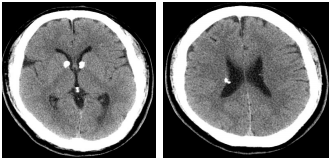

76 33 歲男性,輕微智能不足,抽搐(seizure),根據此二張 CT 影像,最適當的診斷是:

(A) gliomatosis (B) multiple sclerosis(MS) (C) tuberous sclerosis(TS) (D) heterotopia of gray matter